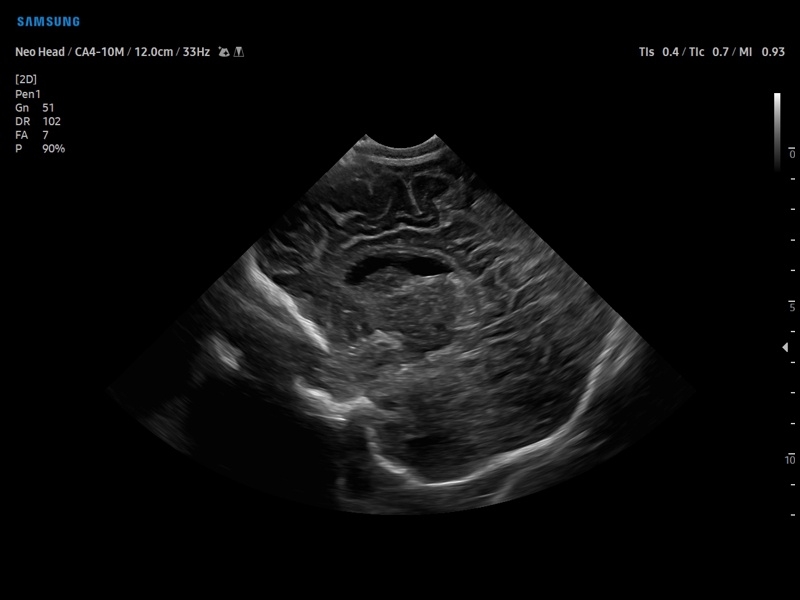

Ультразвуковой сканер V8-RUS является экспертным классом (премиальный уровень) и производится компанией Samsung Medison. Сканер V8 обеспечивает превосходное качество изображения благодаря использованию технологии Crystal Architecture™, которая включает в себя передовое аппаратное обеспечение, монокристальную технологию изготовления датчиков и сложную программную обработку ультразвуковых лучей.

Samsung Medison V8 представляет собой современную ультразвуковую систему, в которой воплощен многолетний опыт компании Samsung в создании эргономичного и интеллектуального диагностического оборудования. Система оснащена передовыми инструментами автоматизации, которые значительно упрощают рабочий процесс и повышают эффективность исследований.

Система Samsung Medison V8 обеспечивает высококачественную диагностику в различных областях медицины:

• Абдоминальные исследования

• Акушерство и гинекология

• Кардиология

• Ангиология

• Урология и нефрология

• Онкология

• Педиатрия и неонатология

• Исследования поверхностных органов

• Диагностика костно-мышечной системы

• Транскраниальные исследования

• Эзофагокардиография